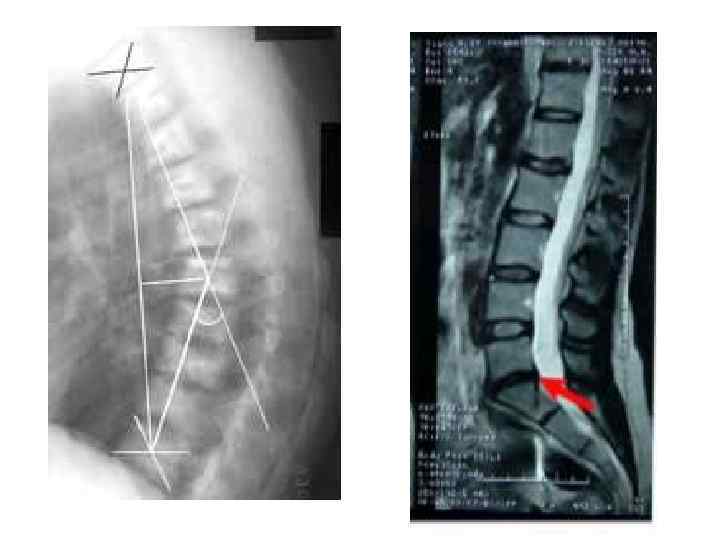

Методы диагностики поражения опорной системы человека 1. 2. 3. 4. Рентген, КТ, Радиоизотопная диагностика, Остеоденситометрия